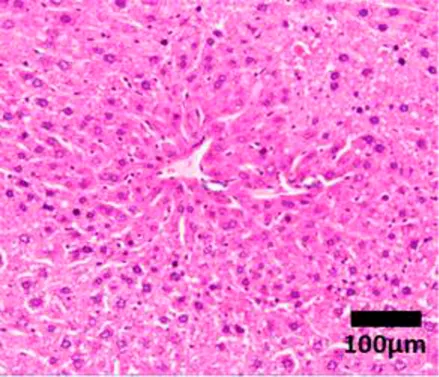

Healthy![]() | None | Healthy liver |

| Hepatocytes are nicely arranged and densely packed | ||

NAFLD Activity Score (NAS) system with representative H&E images. The NAS system is an internationally recognized method of determining the severity of fatty liver disease (see text for references). Steatosis score represents the percentage of lipid droplets present in each field of view, inflammation score represents the number of inflammatory cell clusters (1 cluster = 1 foci) and the ballooning score is indicative of the number of hepatocytes that have altered cell structure due to excess lipid accumulation. The pathologist can give a score between 0 and 3 for each of steatosis and inflammation, and 0–2 for ballooning, based on the characteristics of the samples. Combining the scores from each of the parameters give rise to the total NAS. H&E-stained representative images are provided by our laboratory. All images were taken under ×200 magnification. Black arrows are marking the specific location of the histological features.